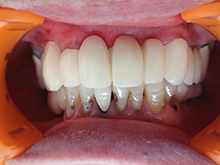

オールセラミックス

金属を使わずに全てセラミックを使用し、光の透過性を上げる事により自然な白い歯に回復させる方法です。

現在では土台から白い材質(ファイバーポストなど)の物を使用することにより、さらに透明感が増し天然歯に近似しています。

オールセラミックは近年進化を遂げており、強度や接着性がかなり改善され、審美的にとても優れたものと成って来ております。

オールセラミックにも色んな種類がありますが、当院ではe-max(二ケイ酸リチウムガラスセラミック、)ジルコニアセラミックスを採用しています。

症 例